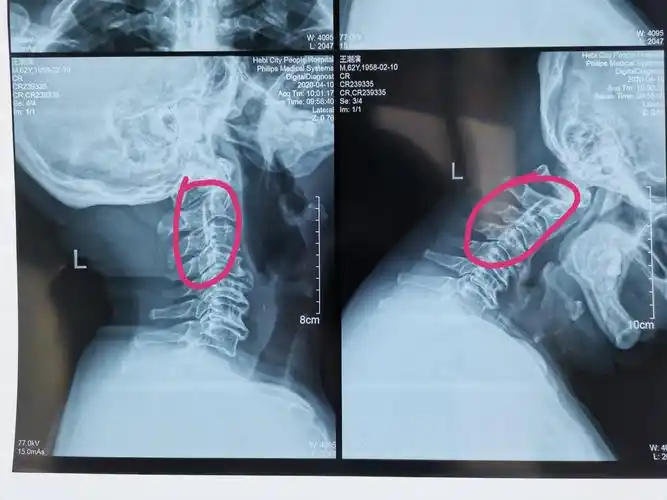

颈椎病专题(一) : 复杂颈椎病病例分享